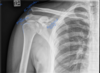

AP Shoulder (EXT) Criteria

Greater tuberosity in profile on lateral side * Humeral epicondyles are parallel to IR ## Footnote `

What position is this AP Shoulder & how do u know

- external rotation - greater tuberosity is in profile